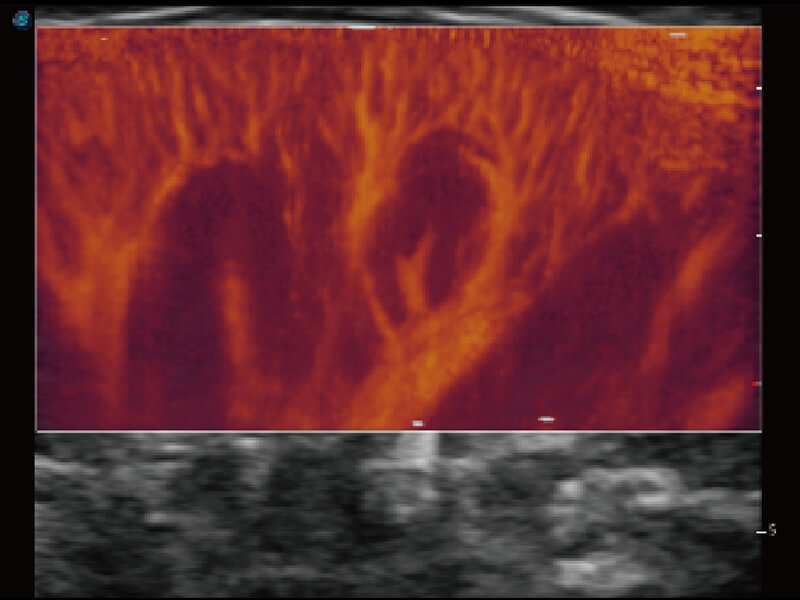

成像功能

S60创新的探头工艺、高精度模数转换系统、前沿的波束重建技术,从前端信号处理每一个环节采集无损声学数据,真实还原组织原貌,再现解剖细节。